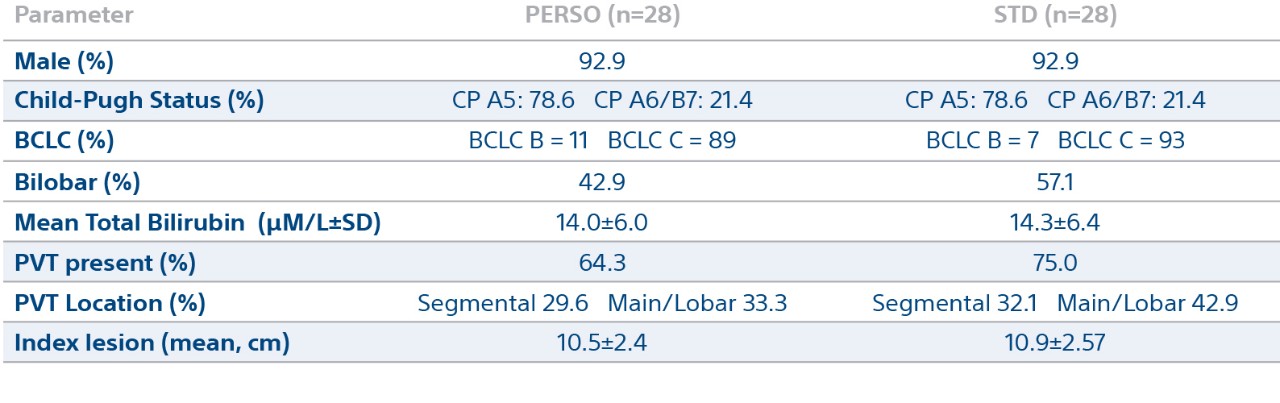

Patient Demographics